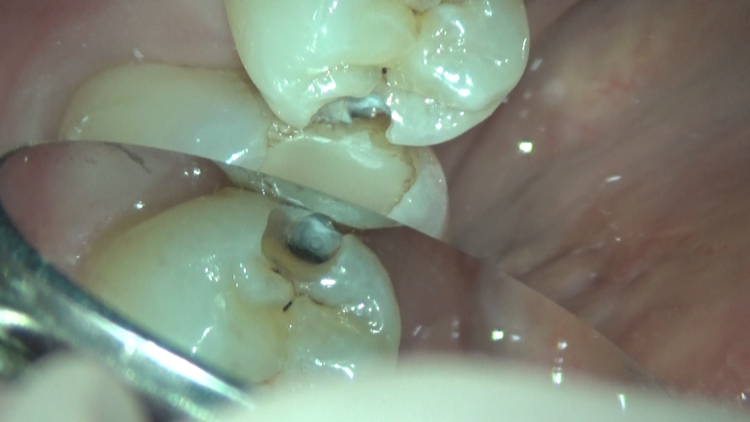

今回のケースは、詰め物の下に虫歯が残っていたため、患者さんのご希望もあり、セラミックでの治療を行いました。

マイクロスコープ下で虫歯の取り残しがないよう注意しながら除去し、歯の神経にも感染は認められなかったので、セラミックでの審美的な回復を行いました。